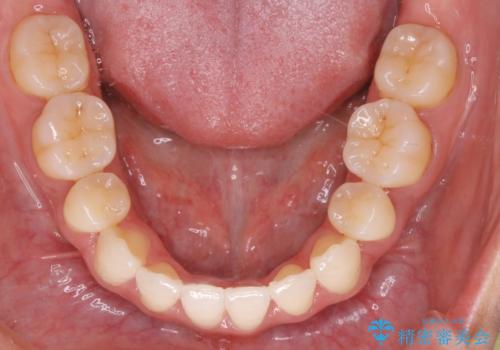

- 口元をさげたいという主訴で来院されました。4番の歯を4本抜歯し、遠心移動とIPRをしました。右上2番が矮小歯のため見た目を重視するならクラウンの提案をしましたが、そのままでの治療を希望されました。

矯正治療の最終段階でスペースクローズにやや時間がかかりましたが、前歯が下がったことで口元の位置も下がりきれいになりました。